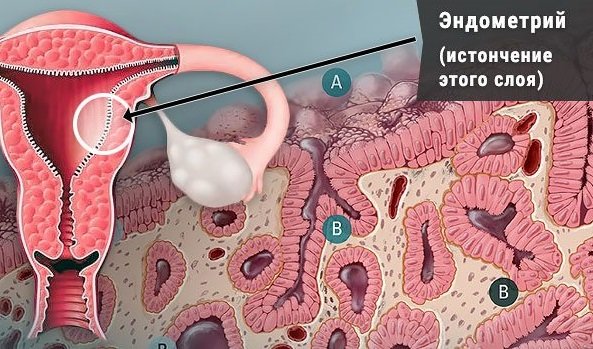

Эндометрий и Беременность: Что Нужно Знать